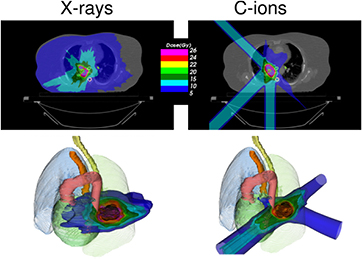

Radiotherapy is an essential component of cancer therapy. The combination of surgery, chemotherapy and radiotherapy is becoming a standard for most cancer patients. Out of the approximately 2/3 of cancer patients receiving radiotherapy, over 80% is irradiated with x-rays produced at linear electron accelerators (Linacs). The others receive specialized treatments such as gamma knife or brachytherapy. Only about 0.8% of the radiotherapy patients are treated with high-energy charged particles, but their number is rapidly increasing (figure 1). The rationale for using accelerated ions in therapy comes from the depth-dose distribution (figure 2), and was originally proposed by Wilson (1946), a student of Ernest Orlando Lawrence at the University of California in Berkeley (CA, USA). The advantages of the Bragg peak shown in figure 2 are quite obvious: unlike x-rays, the energy deposited per unit track increases with depth, therefore for a single beam the dose to the normal tissue will be much lower for ions than for photons when delivering the same dose to the tumor. While in x-ray therapy it is necessary to cross-fire the tumors from many different angles to increase the ratio of the doses to the tumor and normal tissues, only a few beams are necessary if charged particles are used (figure 3). Thus, the same radiation dose to the tumor (and therefore the same tumor control probability, TCP) can be achieved with lower integral dose to the normal tissue (lower normal tissue complication probability, NTCP); or the dose to the tumor can be increased (higher TCP) keeping the same NTCP as expected for x-rays. The most advanced x-ray delivery techniques, such as the intensity modulated radiotherapy (IMRT)5, are almost unbeatable in terms of target coverage, but the cost is an even higher 'dose bath' where the patient is immersed.

Standard image High-resolution imageFigure 2. Physical advantages of CPT. (A) Depth-dose distributions of high-energy x-rays and monoenergetic beams of protons or carbon ions. At the same range, C-ions have lower straggling than protons, but a tail of fragments is visible beyond the Bragg peak. In clinical applications, the Bragg peak must be extended to cover all the tumor (B). This can be done by overlapping different pristine beams at different energy and intensity. Figures from GSI Helmholtz Center library, Darmstadt, Germany.

Standard image High-resolution imageFigure 3. Charged particles produce a reduced integral dose to normal tissue. Treatment of a lung cancer by stereotactic body radiation therapy (left) or carbon ions (right). The plans are designed for a treatment with high-dose single-fraction. Only 3 beams can be used with particles, as also shown in the 3D image below. Plans courtesy of Krjstian Anderle, PhD thesis, Technical University of Darmstadt, Germany.